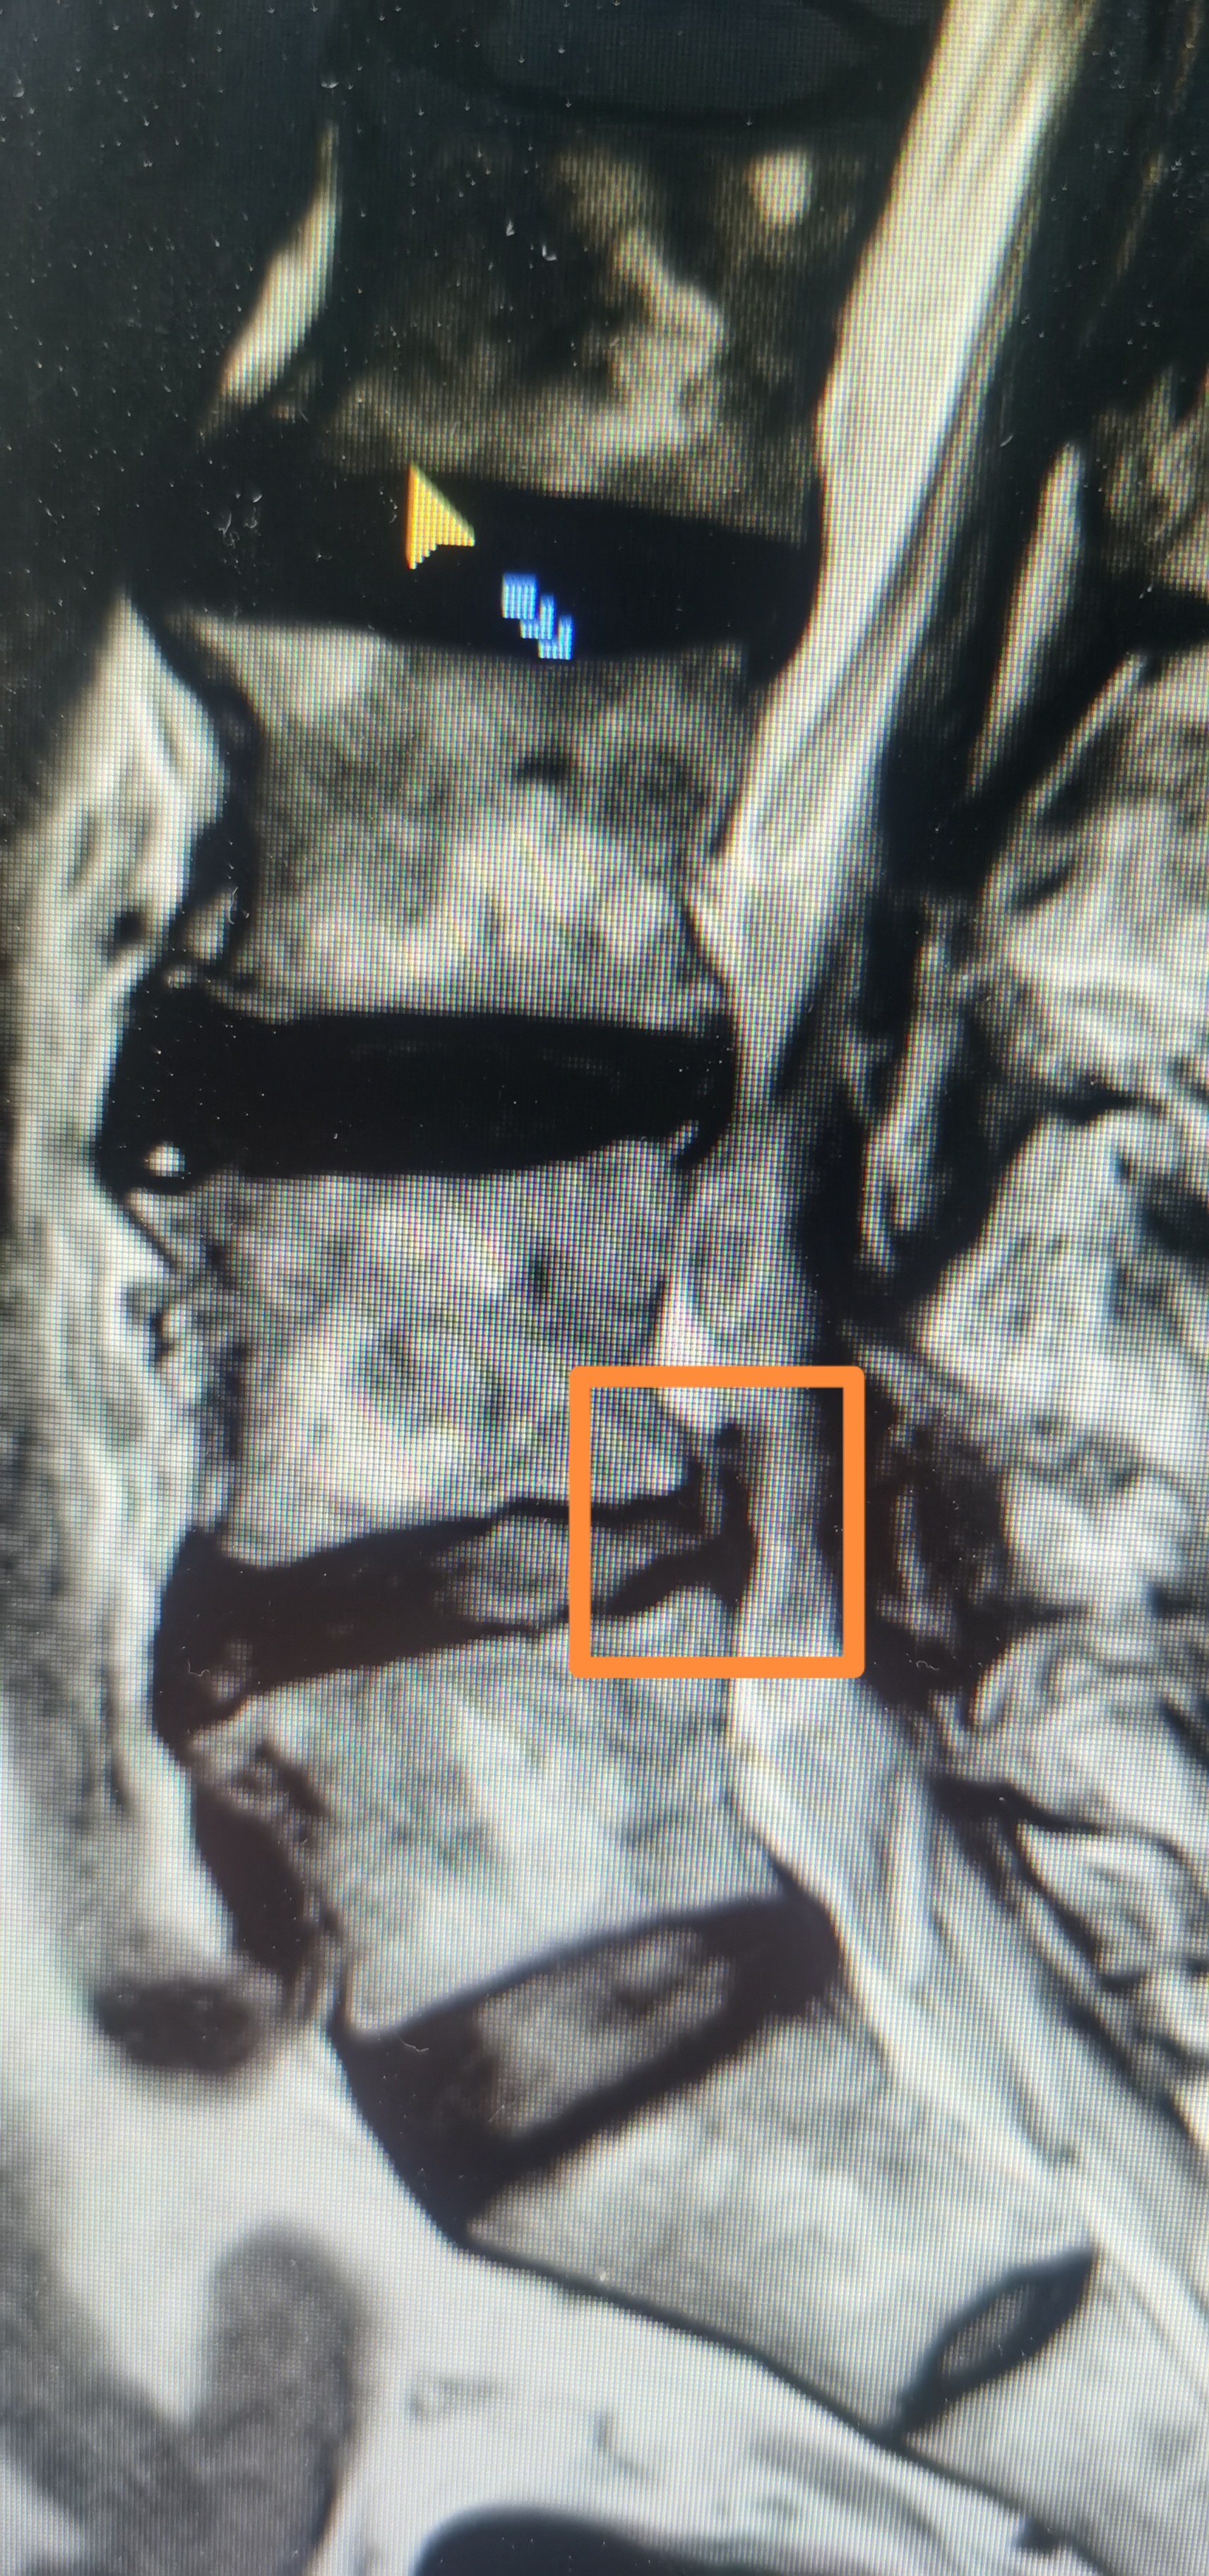

经过 1 个多小时的手术,他们成功将苏大爷椎间盘突出部分彻底取出,仅留下 6.2 mm 的创口,手术过程中基本没有出血,术后苏大爷的症状和体征马上就消失了。苏大爷回忆起来时不禁感叹,谈话间手术就结束了,术后第二天就可以下床走动了,而且手术过程也没有多少疼痛感,自己好像做了个「假手术」。

椎间孔镜取出大块脱出的椎间盘